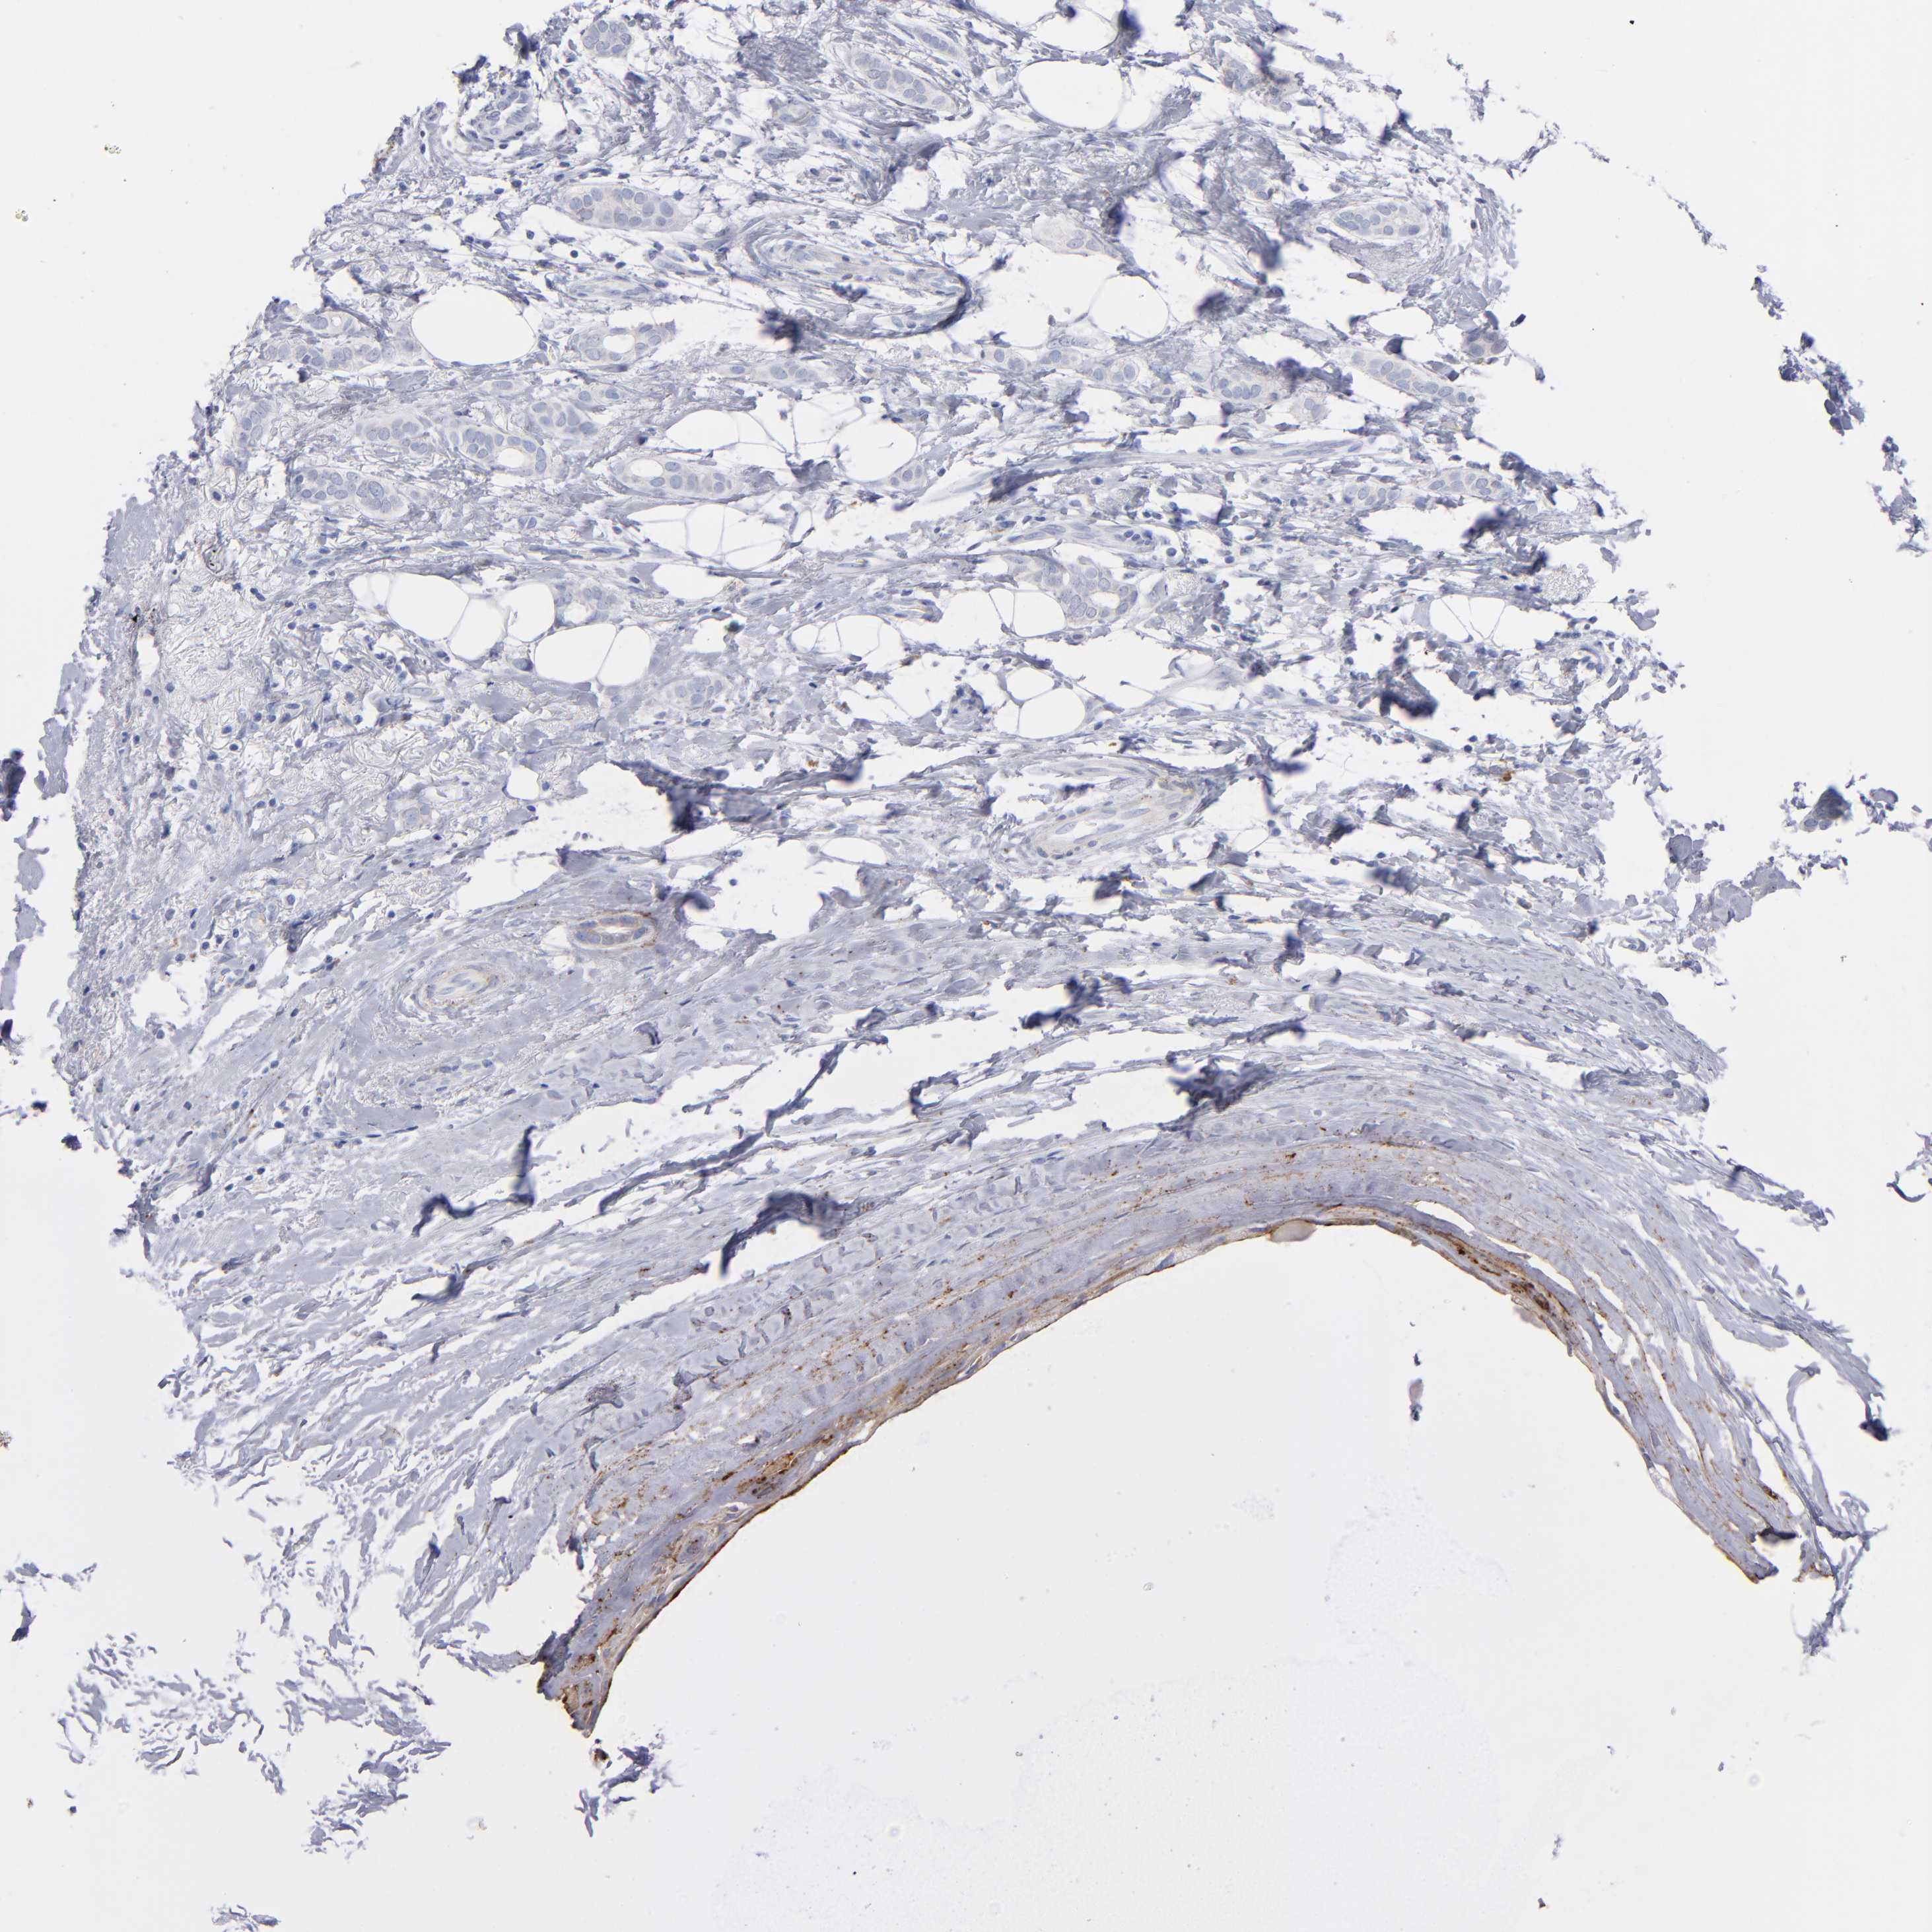

CANCER BREAST CANCER Show tissue menu

BRCA TCGA BRCA VALIDATION PROTEIN EXPRESSION

ANTIBODIES

AND

VALIDATION